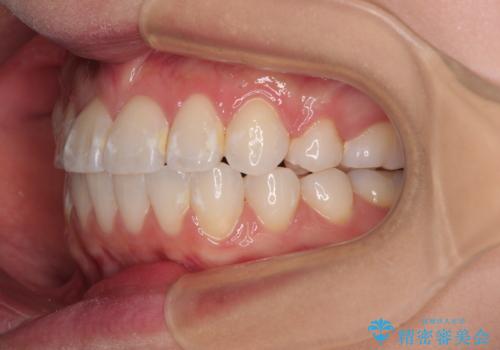

- 八重歯と、それによる正中のズレを気にして来院された患者様です。

口元の突出感は気にしていなかったため、上顎の左右第一小臼歯を抜歯することで、八重歯の解消と上顎の正中を改善していくこととしました。

奥歯の咬み合わせを維持しながら正中位置を改善するために、補助装置を使用しました。

予定より期間がかかりましたが、上下の正中位置を綺麗に一致させることができました。